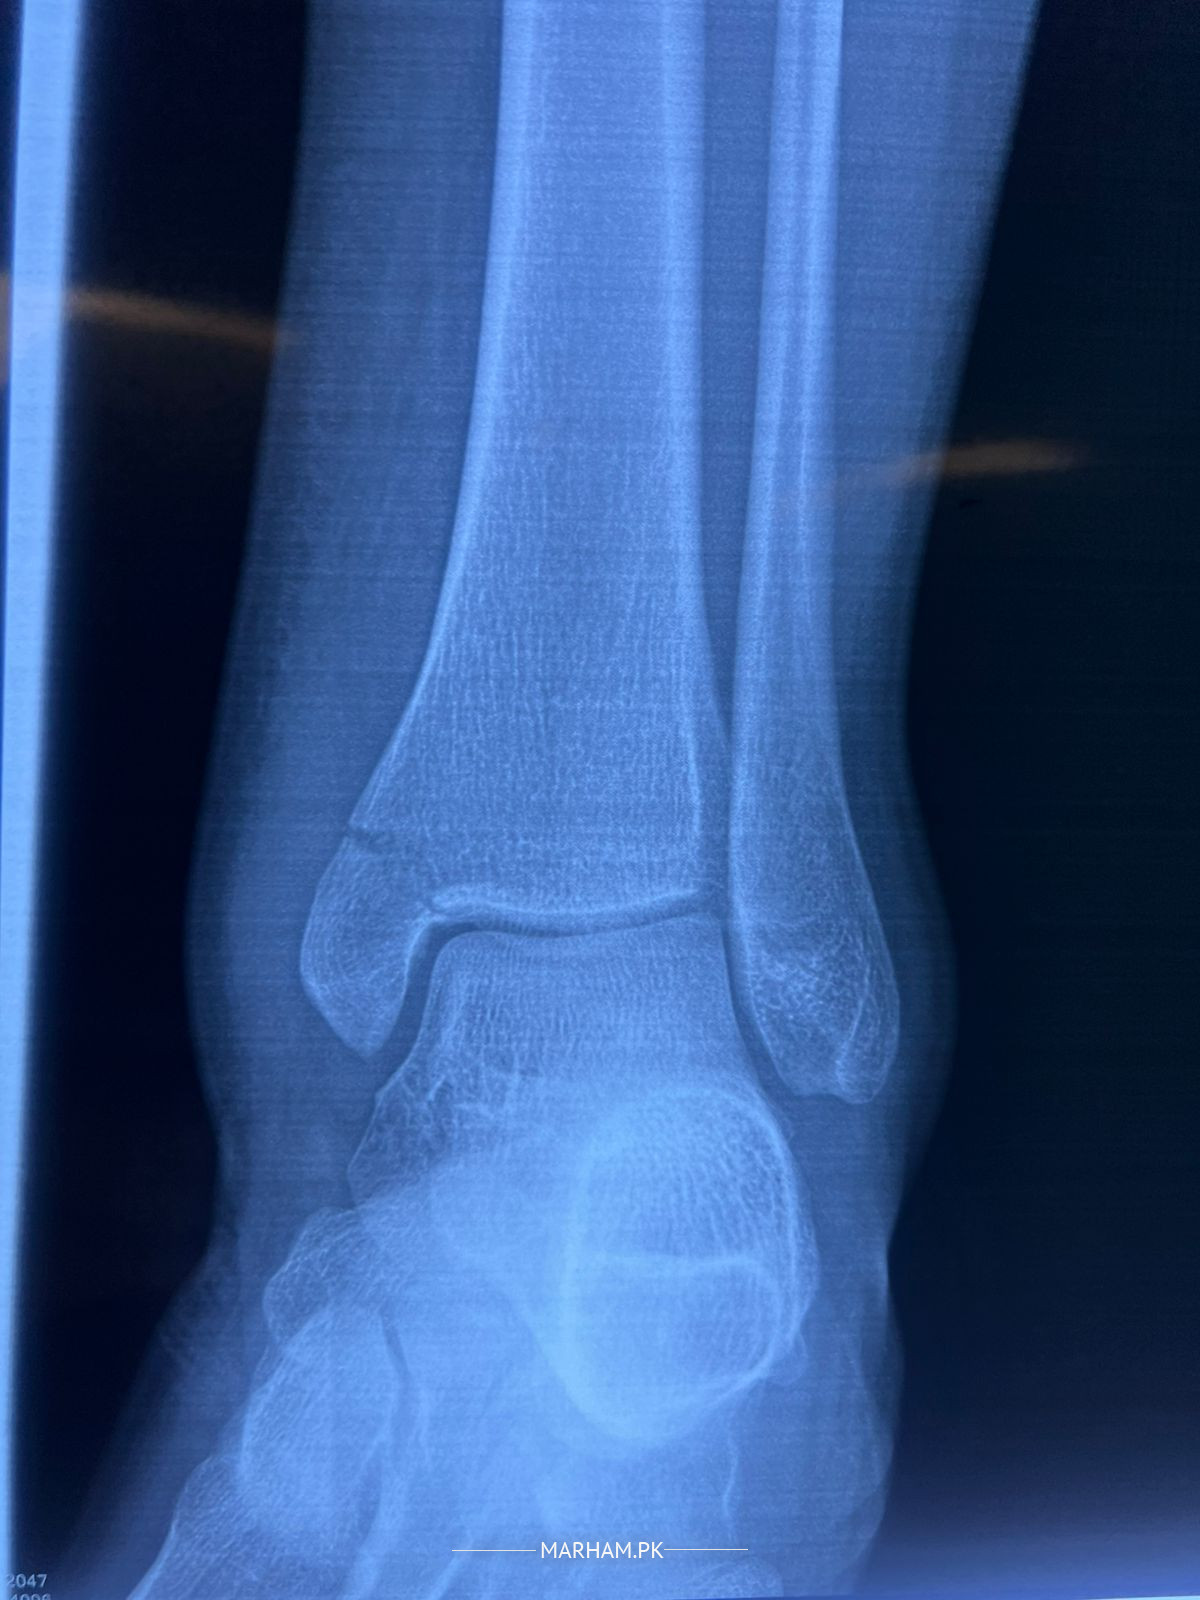

my brother fell while playing football and got a fracture on his ankle. plz see the xray and advice whether only plaster is enough or surgery is a must.

need surgery

Position is acceptable, but chances of delayed and non union is there . If no medical contradiction , than better to go for surgery. Even after surgery your foot will be in Plaster for 6 weeks.

surgery is better as patient is young.

As Patient is Young better go for operation